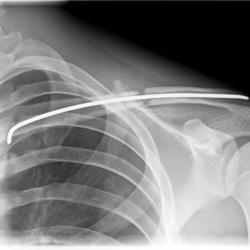

Röntgenbilder